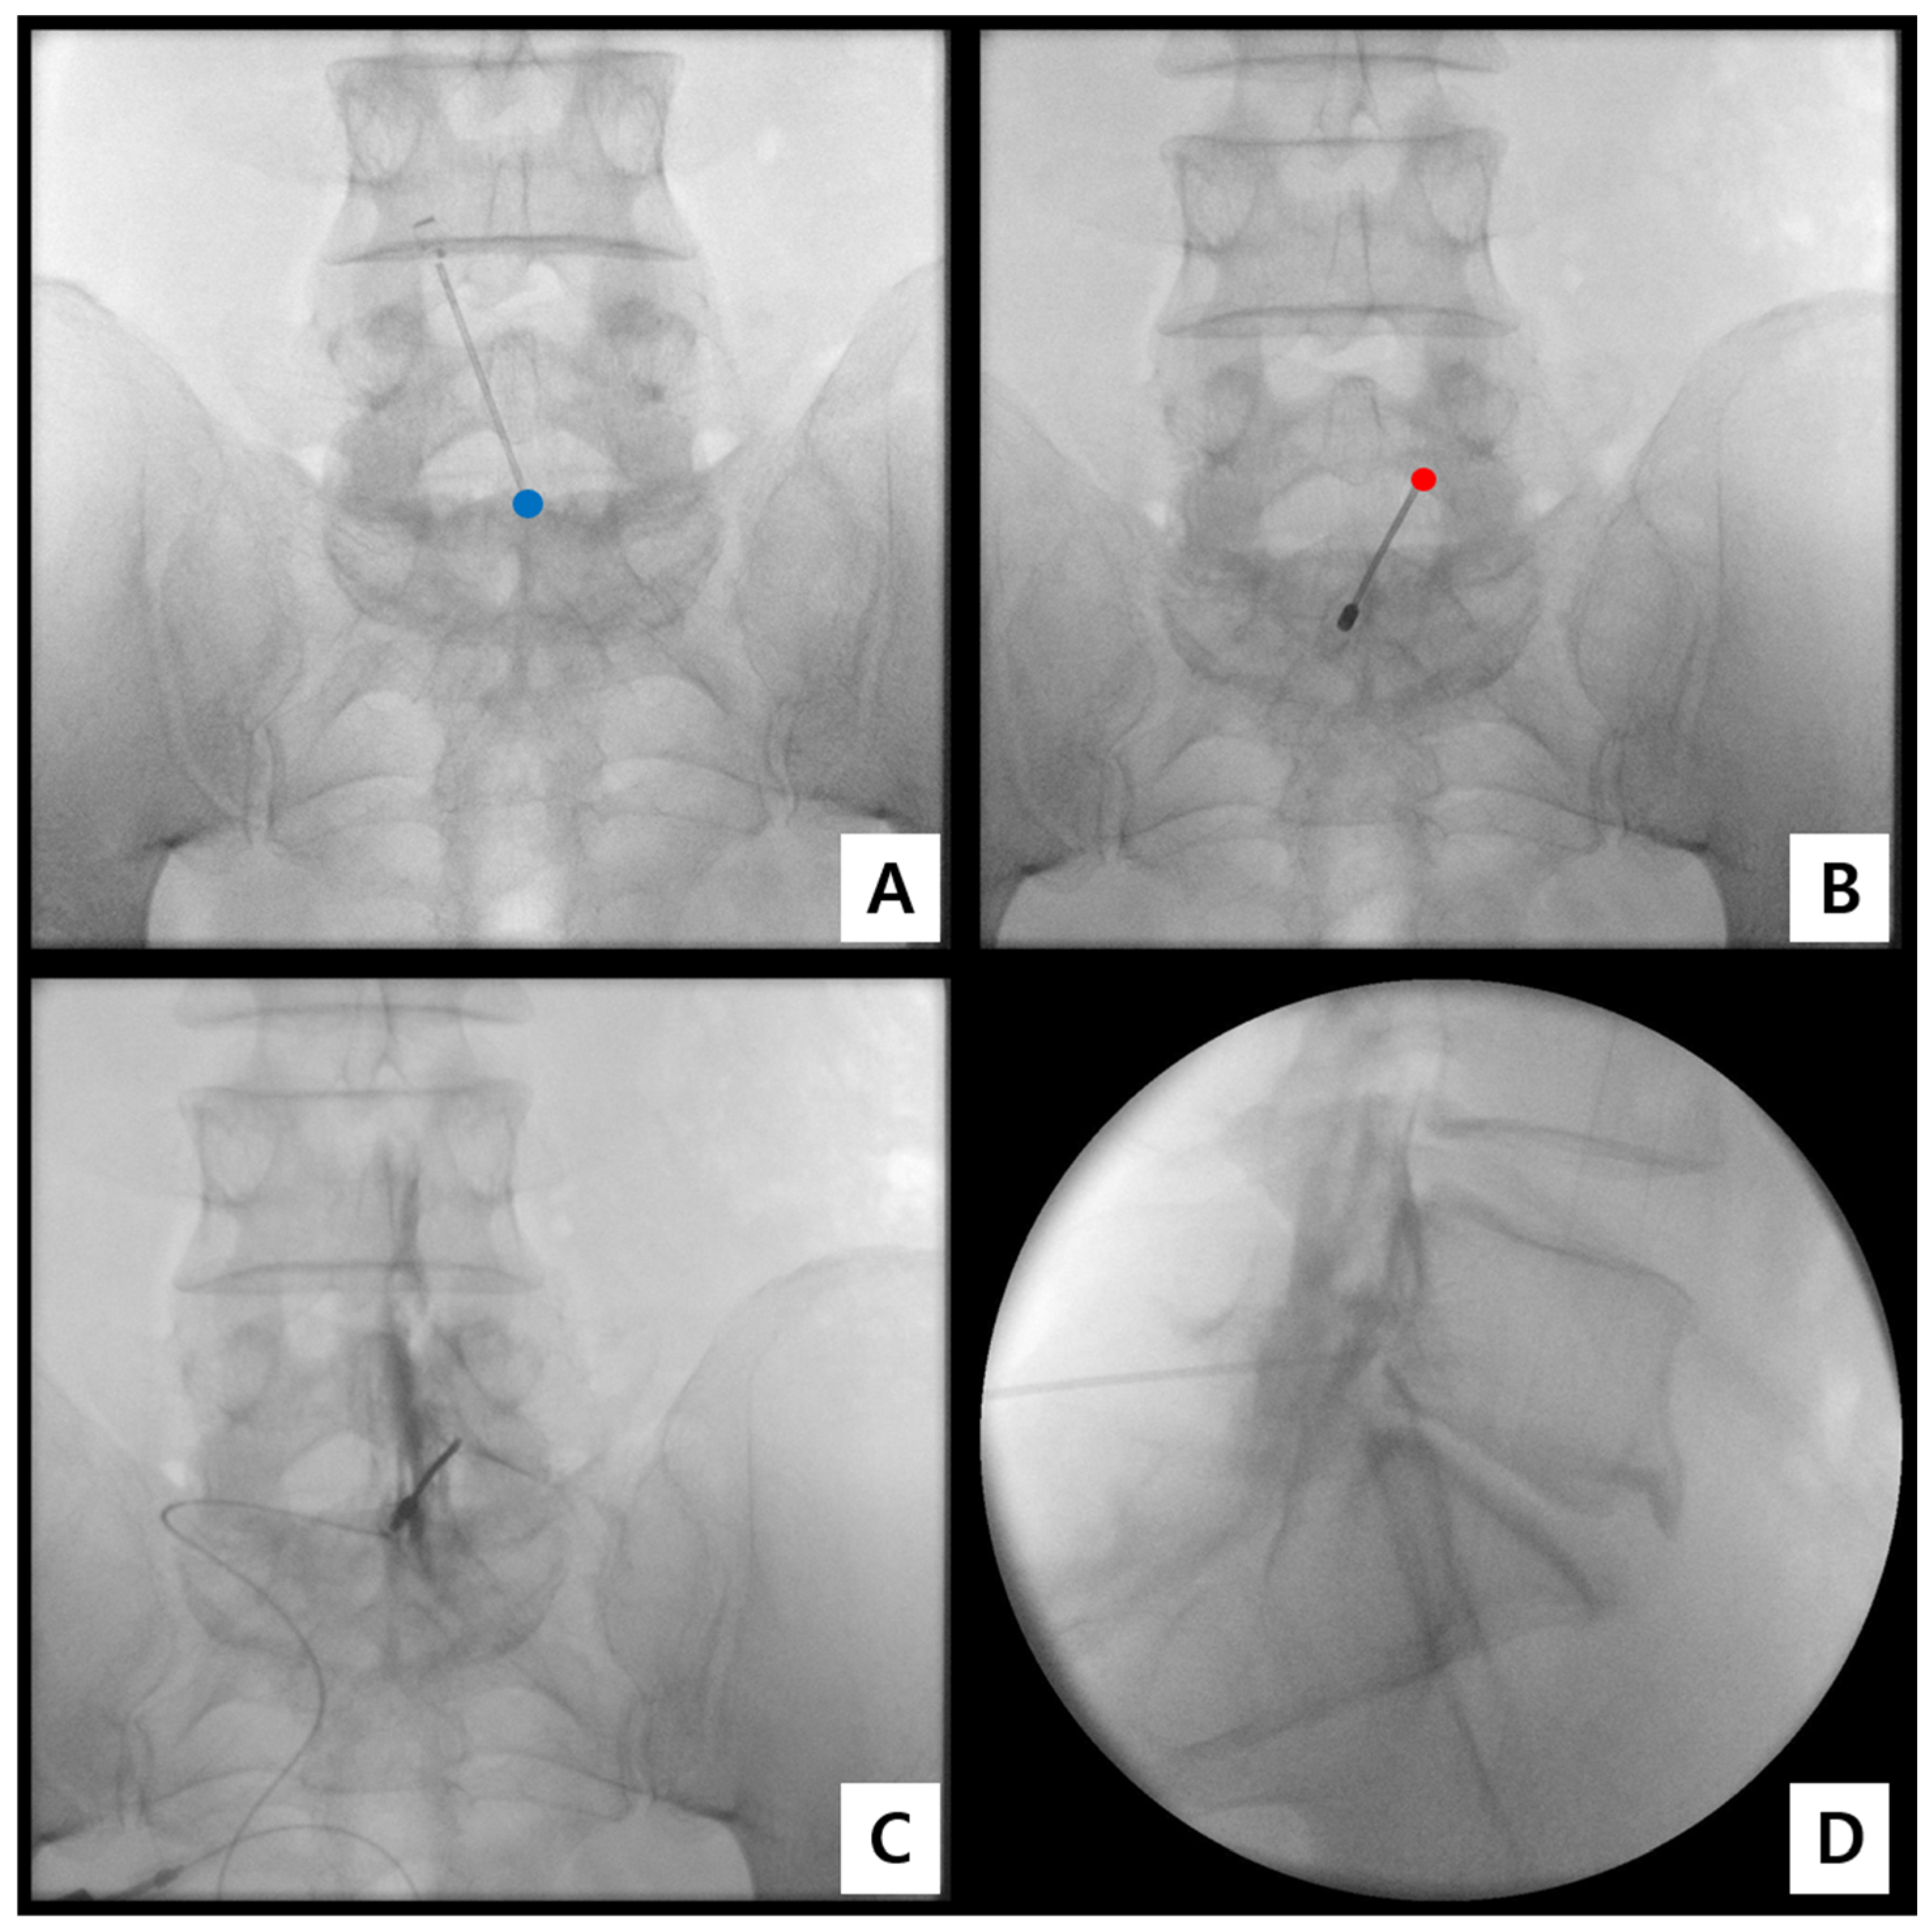

2.3. Procedural Technique for Catheter-Free LIVEI at L5–S1

- Step 1. Fluoroscopic target identification (AP)

- Step 2. Midline entry and bone docking

- Step 3. Interlaminar epidural access confirmation

- Step 4. Controlled ventral advancement (“saline cushion” technique)

- Step 5. Fluoroscopic confirmation of ventral epidural positioning

- Step 6. Final injectate delivery

2.4. Fluoroscopic Assessment and Grading of Spread

- Grade 3: Anterior (ventral) epidural spread with foraminal extension at two or more levels;

- Grade 2: Anterior spread with limited foraminal or cranio-caudal extent;

- Grade 1: Posterior-only or failed anterior spread.

3.2. Fluoroscopic Findings

| Contrast Spread Grade | Definition | N (%) |

|---|---|---|

| Grade 3 | Anterior (ventral) spread with foraminal extension involving ≥ 2 levels | 8 (66.7%) |

| Grade 2 | Anterior (ventral) spread with limited foraminal involvement | 4 (33.3%) |

| Grade 1 | Posterior-only or absence of anterior (ventral) spread | 0 (0%) |

| Total | Ventral epidural spread confirmed | 12 (100%) |